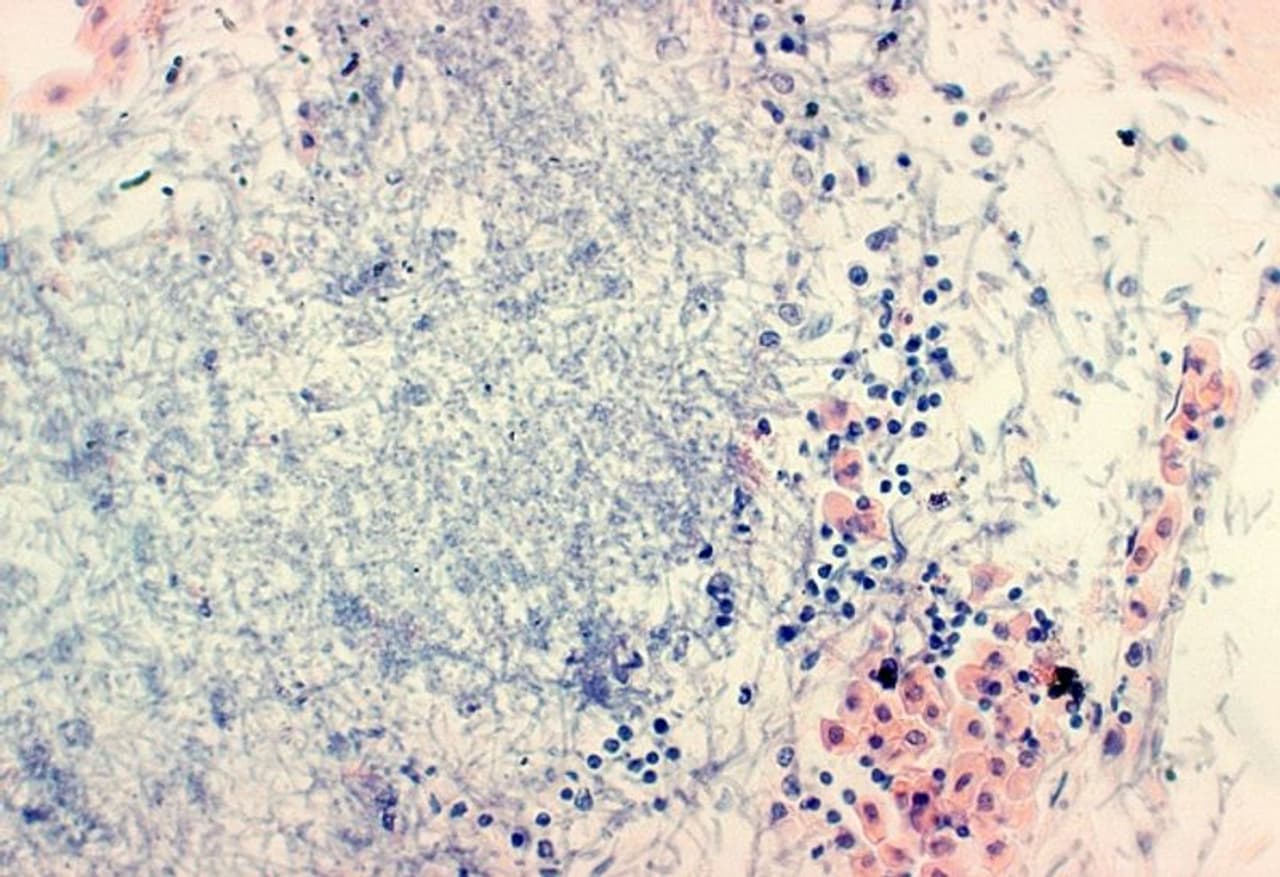

মিউকরমাইকোসিস রোগে আক্রান্ত ব্যক্তির হদিশ মিলল কলকাতায়। শহরে আরও এক আক্রান্তের হদিশ মেলায় চিন্তায় চিকিৎসকরা। কলকাতায় ক্রমশ ছড়াচ্ছে ব্ল্যাক ফাঙ্গাস বা কালো ছত্রাকে আক্রান্ত হওয়ার ঘটনা। যা বেশ উদ্বেগের। এবার যে ব্যক্তি কালো ছত্রাকে আক্রান্ত হয়েছেন, তিনি করোনা থেকে কিছুদিন আগেই সুস্থ হয়েছেন।

করোনা থেকে সেরে উঠে বাড়ি চলে যাওয়ার পরে ফের অসুস্থ হয়ে পড়েন ওই ব্যক্তি বলে খবর। তাঁকে আর এন টেগোর হাসপাতালে ভর্তি করা হয়। তার কিছুদিনের মধ্যেই বিভিন্ন পরীক্ষার মাধ্যমে কালো ছত্রাকের সন্ধান মেলে তাঁর শরীরে।

মিউকরমাইকোসিস বা কালো ছত্রাক, আতঙ্ক ছড়াচ্ছে বেশ কয়েক দিন ধরেই। দেশের বেশ কয়েকটি জায়গায় রোগীর শরীরে মিলেছে কালো ছত্রাক বা মিউকরমাইকোসিসের সন্ধান। এবার খোদ কলকাতায় হানা দিল মিউকরমাইকোসিস। কলকাতায় এক রোগীর শরীরে এই ছত্রাকের সন্ধান মিলেছে।